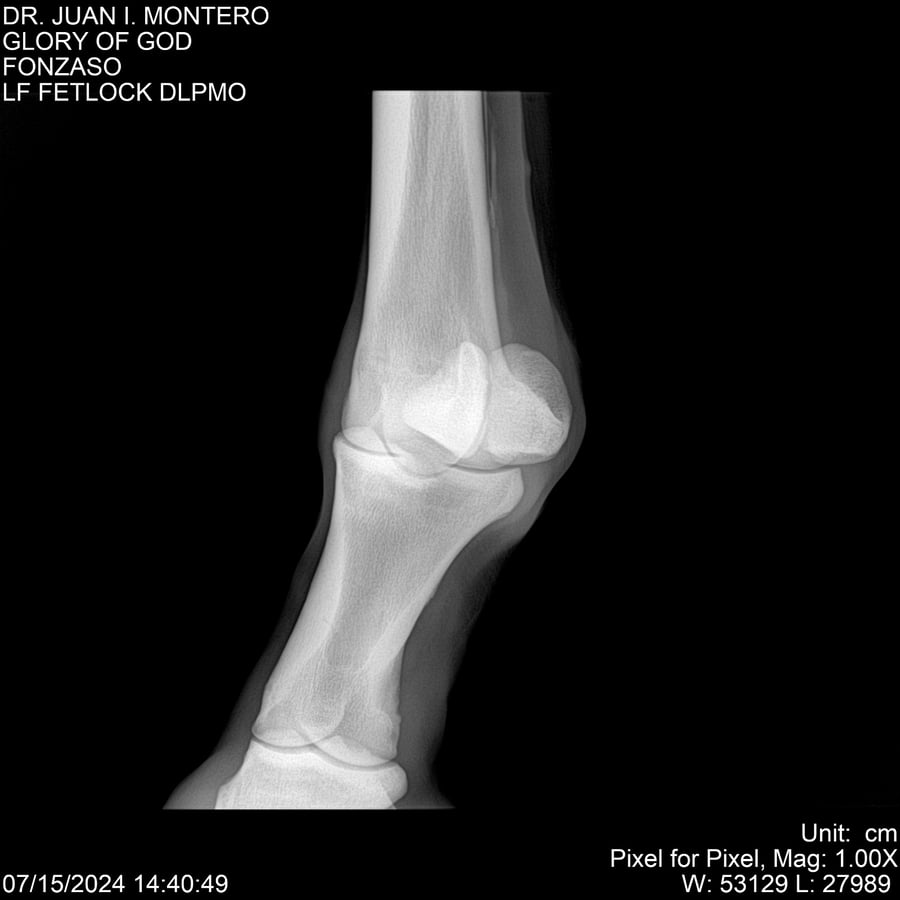

LOTE 10, GLORY OF GOD 🔥 🔥 🔥 Lote Anterior Volver al remate Lote Siguiente Ficha Contacto Montevideo - Ficha del Lote Identificador: #281389 Categoría: Yeguarizos Montevideo - 115 Visualizaciones ClicData Contacto Empresa: Abelenda N. R., Walter Hugo Nombre*: Teléfono* : E-mail* : Mensaje Enviar Registrese gratis Este contenido Exclusivo está disponible sólo para usuarios registrados Ingresar